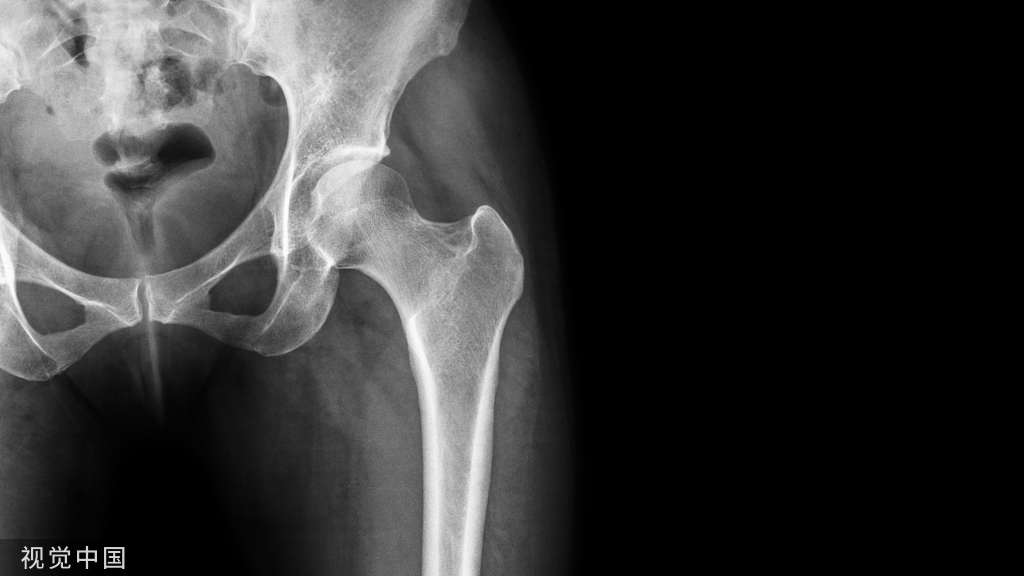

骨不连是四肢骨折术后常见并发症,治疗棘手,发病率高达 5%~10%,目前仍是全世界骨科医师临床工作中所面临的难点与挑战。

骨不连的定义

1.时间,骨折后6-8个月骨折仍未愈合。

2.已经连续观察3个月骨折没有愈合迹象,即每次拍片骨折的缝隙和骨痂生长都与前次相同。